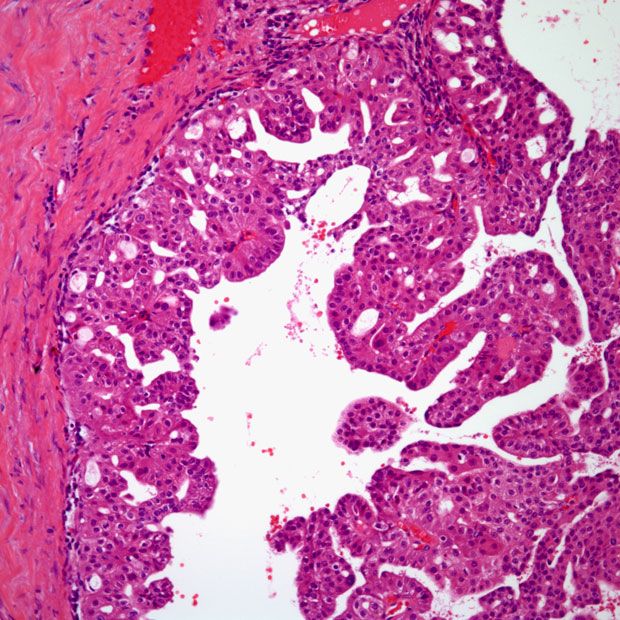

Disease sites include non–small cell lung cancer, hormone receptor–positive breast cancer, ovarian cancer, thyroid cancer, pancreatic ductal adenocarcinoma, soft tissue sarcoma, hepatocellular carcinoma, and kidney cancer.